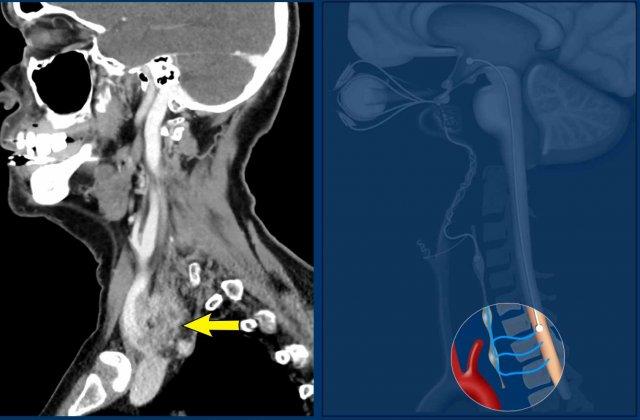

Ca lâm sàng

Hình ảnh của một bệnh nhân có khối u vùng cổ phát triển nhanh, với các triệu chứng khó nuốt và khàn tiếng.

Khám thực thể cũng phát hiện hội chứng Horner không hoàn toàn với sụp mi và co đồng tử.

Hình ảnh

CT đầu và cổ cho thấy khối u tuyến giáp xâm lấn với sự lan rộng cạnh thanh quản và trước cột sống, kèm theo xâm lấn sụn giáp (đầu mũi tên vàng).

Có huyết khối u trong tĩnh mạch cảnh (mũi tên đen).

Continue with the next images…

Lưu ý sự xâm lấn sụn giáp (đầu mũi tên màu vàng).

Ở rìa của lát cắt có một di căn não.

Thảo luận

Hội chứng Horner xảy ra do ảnh hưởng đến hệ thống hạch trước.

Có nhiều sợi thần kinh kết nối hạch cổ giữa (MCG) và hạch cổ dưới (ICG), nằm ở phía trước và phía sau động mạch đốt sống.

Chẩn đoán cuối cùng

Ung thư tuyến giáp thể không biệt hóa.

Đây là một trong những khối u ác tính hung hãn nhất và có tiên lượng xấu.